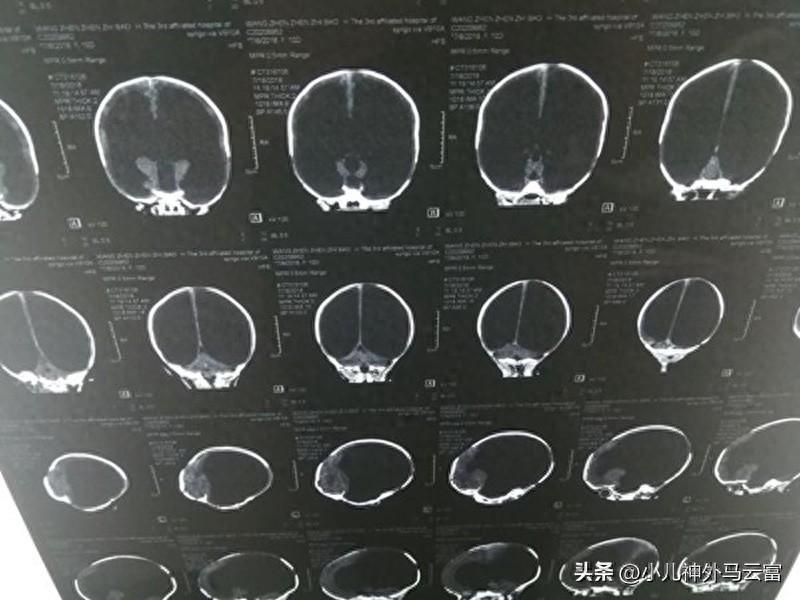

嬰幼兒重度腦積水

2歲以上的兒童腦積水的典型症狀爲頭痛、噁心嘔吐、嬰幼兒頭圍增大、前囟門緊張飽滿、顱縫開裂、頭皮靜脈怒張、落日眼、眼球震顫、斜視,可伴有語言、運動功能障礙、抽搐、智力低下。腦積水可通過CT檢查見腦室普遍擴大,並可能伴有大小便失禁、進行性癡呆、視力模糊,視神經乳頭水腫,偶伴複視,眩暈及癲癇發作,即可確診。

腦積水確診需要進行頭顱CT與MRI檢查,加腦脊液電影檢查。頭顱CT顯示腦室系統擴大,輕度者需要前後對比頭部CT,觀察確定有腦室進行性擴大才能確診。頭部MRI檢查不僅可以顯示腦室擴大,而且對觀察腦室周圍間質性水腫更清晰,對腦積水的診斷及鑑別腦萎縮比CT更加準確,腦脊液電影檢查可以明確腦積水梗阻部位及程度,對選擇腦積水的治療方法有極大的幫助。

醫生要根據病人的典型的腦積水臨牀表現和頭顱CT、MRI檢查診斷本病。兒童表現爲頭痛、噁心嘔吐、頭暈,嬰幼兒表現爲頭顱增大、落日目等典型症狀。頭顱CT徵象是腦室系統擴大。頭部MRI檢查不僅可以顯示腦室擴大,而且觀察腦室周圍間質性水腫更清晰,對腦積水的診斷更有幫助。